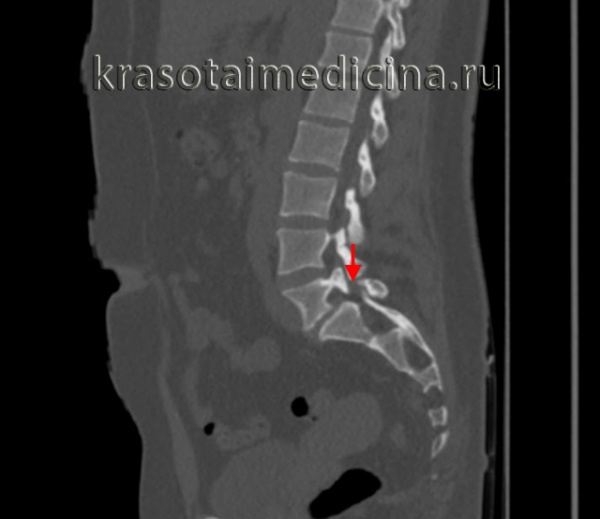

о Различной выраженности спондилолистез и фораминальный стеноз на сагиттальных реконструкциях:

- Снижение высоты межпозвонкового диска

- Дегенеративные изменения замыкательных пластинок

(Слева) КТ, сагиттальный-срез: у пациента с врожденным незаращением межсуставной части дуги определяется ограниченный хорошо выраженными кортикальными краями широкий дефект МЧ дуги L5 в сочетании с гипертрофией и дисморфизмом нижнего суставного отростка L4.

(Справа) КТ, фронтальный срез: у пациента с врожденным незаращением правой межсуставной части дуги отмечается увеличение размеров и гипертрофия правой пластинки дуги и ротация остистого отростка.

(Справа) КТ, сагиттальный-срезе (костный режим): задний край тела L5 находится практически на одном уровне с передним краем S1. Хорошо виден дефект межсуставной части дуги, а также признаки выраженного стеноза межпозвонкового отверстия.

КТ пояснично-крестцового отдела позвоночника. Нарушение целостности задних отделов позвонка без существенного спондилолистеза.